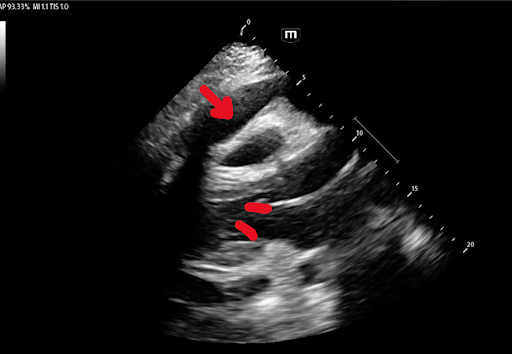

Right Atrial Systolic Collapse

The best view to see right atrial systolic collapse is the apical 4-view. If you are unable to properly visualize the right atria with the apical 4-view, try the subxiphoid approach!

Systole is defined when the mitral valve is closed. Notice the fragile wall of the right atrium collapsing during systole. This is an early and very concerning sign of pericardial tamponade.